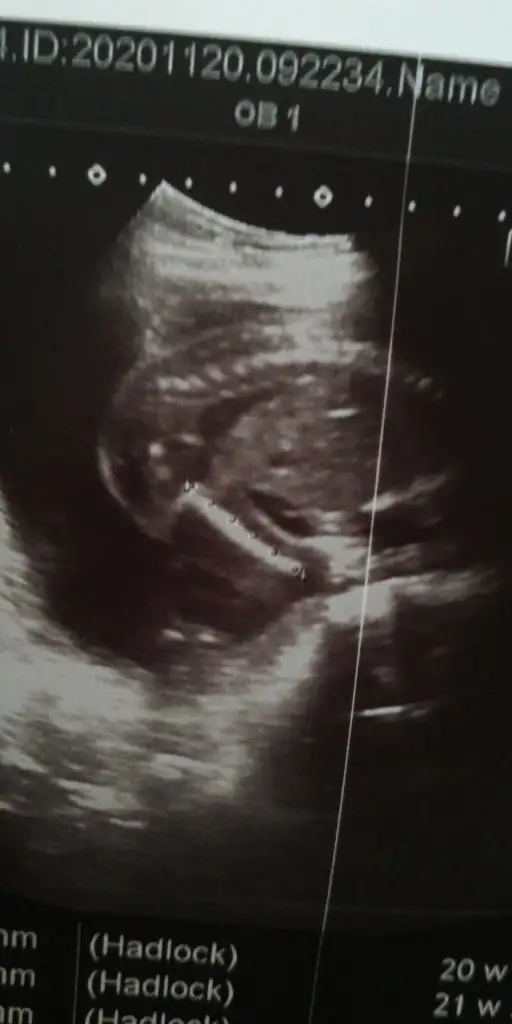

Bacı ben bebeği göremiyorum ne pipisiKızlar merhaba doktor erkek dedi ama bu resmi verdi hatta banada pipi gösterdi ama burda sanki kız gibi kafam karıştı

Bacak arası bu canımBacı ben bebeği göremiyorum ne pipisi

Burasi neresikiKızlar merhaba doktor erkek dedi ama bu resmi verdi hatta banada pipi gösterdi ama burda sanki kız gibi kafam karıştı